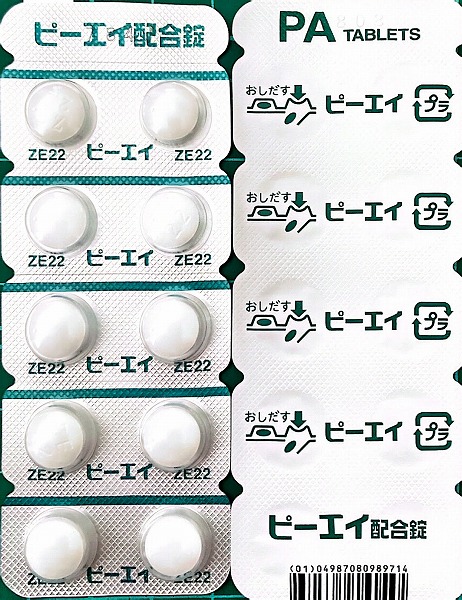

2024.7.12(金) 2回目のコロナ感染 7.16(火)検査で陽性